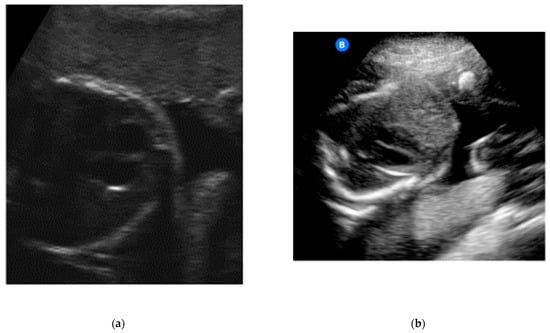

With regard to identifying the amniotic fluid during the 15-s video, 43 of the 46 participants (93.5%) managed to locate the amniotic fluid correctly in at least one of the four quadrants (Figure 3a,b). A total of 52.2% succeeded in locating the amniotic fluid in all four quadrants in the videos. In relation to capturing still images of the amniotic fluid, the rate of images with sufficient quality was lower than with the videos (80.4% with at least one adequate still image in the four quadrants and 43.5% with sufficient quality in all four quadrants).

Figure 3.

(a) Example of an image obtained by a study participant in cohort A, showing the amniotic fluid (satisfactory presentation). (b) Example of an image obtained by a study participant in cohort B, showing the amniotic fluid (satisfactory presentation).